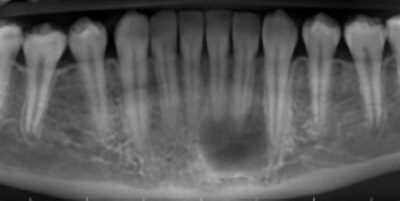

12-year-old boy with a lesion on the anterior mandible

A 12-year-old boy presented to the oral surgeon because of an anterior mandibular lesion noted on a panoramic radiograph.

14-year-old-boy with a radiolucent mandibular lesion

A 14-year-old boy was referred to the oral surgeon because of a radiolucent mandibular lesion noted on a panoramic film.

74-year-old man with a mandibular lesion

A 74-year-old man was referred to the oral surgeon by his dentist because of a mandibular lesion in the right mandible.